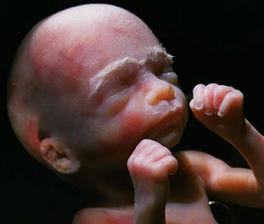

Vajíčko ve vejcovodu čeká zhruba 12 až 24 hodin na příchod spermií. V ejakulátu je v průměru 250 milionů spermií, z toho pouze zhruba 400 se dostane až k vajíčku ve vejcovodu, přičemž cesta z pochvy do vejcovodu trvá spermiím až 10 hodin. Obvykle pouze jedna spermie uspěje a pronikne po zhruba 20 minutách snahy do vajíčka. Tím dojde ke vzniku oplodněného vajíčka, tzv. zygoty. V příštích 10 až 30 hodinách dochází ke splynutí genetických informací vajíčka a spermie. Pohlaví dítěte je určeno již v této chvíli – pokud spermie nese chromozom Y, narodí se chlapec, pokud chromozom X, narodí se dívka.

některé obrázky čerpány z http://mimiblog.cz/kt/tyden/1